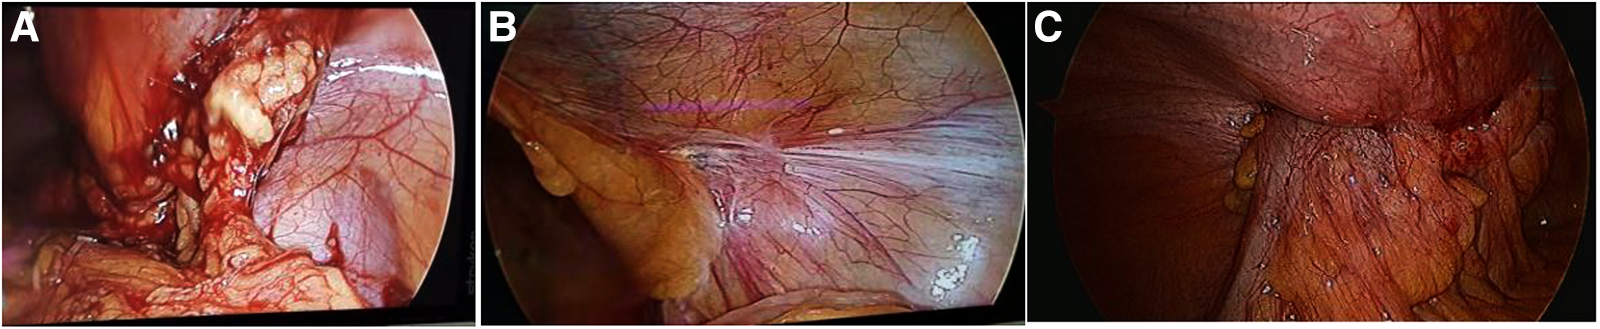

Figure 6

The mesh infection in laparoscopic exploration: (A) open preperitoneal hernioplasty showed adhesion of greater omentum; (B) lichtenstein repair showed no adhesion of inguinal region; (C) TAPP showed invasion of colon.